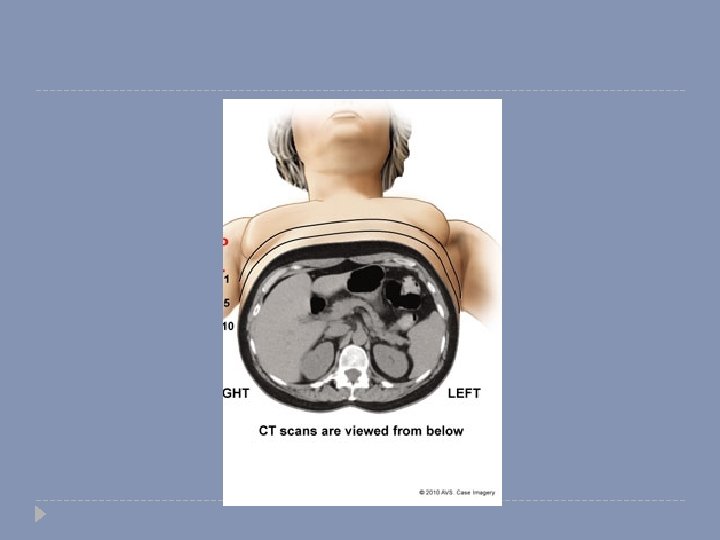

CT Scan � It is an ionizing radiation. � Corss-sectional imaging. � Better anatomical visualization.